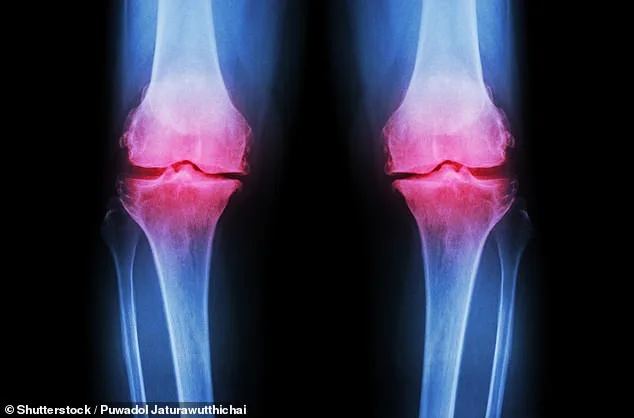

A groundbreaking advancement in treating osteoarthritis has emerged from Columbia University, where scientists have successfully grown a fully functional human knee in the lab. This innovation involves creating a 3D-printed scaffold using biodegradable materials, which is then seeded with bone and cartilage cells. Over the course of a year, these cells regenerate natural tissues while the scaffold dissolves, resulting in a complete lab-grown knee. Researchers believe this could be transplanted into patients, offering a permanent solution for those suffering from severe joint degradation. Osteoarthritis, which affects 32 million Americans—14 million specifically in the knees—is a leading cause of disability, with current treatments limited to pain management or invasive surgery. This new approach represents a potential paradigm shift in regenerative medicine, targeting the root cause rather than merely alleviating symptoms.

Osteoarthritis is the most common form of arthritis globally, and its prevalence has surged in recent decades. Data from the World Health Organization shows a 132% increase in cases since 1990. Experts attribute this rise to aging populations, rising obesity rates, and socioeconomic disparities. Dr. Raj Patel, a rheumatologist at a leading U.S. hospital, warned, "We're seeing more patients than ever before. Traditional treatments aren't keeping up with the demand." With over 500 million people affected worldwide, the need for alternatives is urgent.